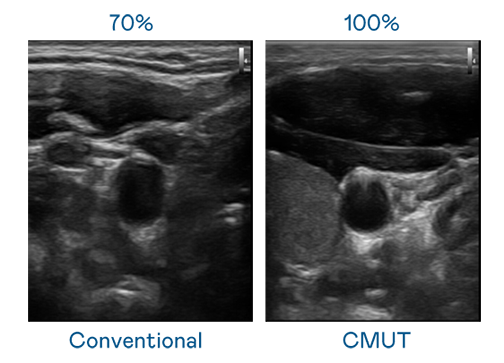

CMUT 技术是一种用电容式微机电元件来产生超音波讯号的技术。与传统 PZT 压电式技术相比,CMUT 频宽增加 30%,更宽频的超音波讯号让影像解析度大幅提升,是实现高影像品质医疗超音波扫描、促进精准医疗发展的关键技术。

大频宽带来超清晰影像

超音波影像的解析度高低,首先取决于探头能发出的讯号频宽。省港流鸢粤语高清 CMUT 可提供高清晰的超音波讯号,提供高频宽、高灵敏度、影像纹理细节更高的超音波影像,协助医护人员缩短影像判读时间及利用精准的医疗影像进行诊断。